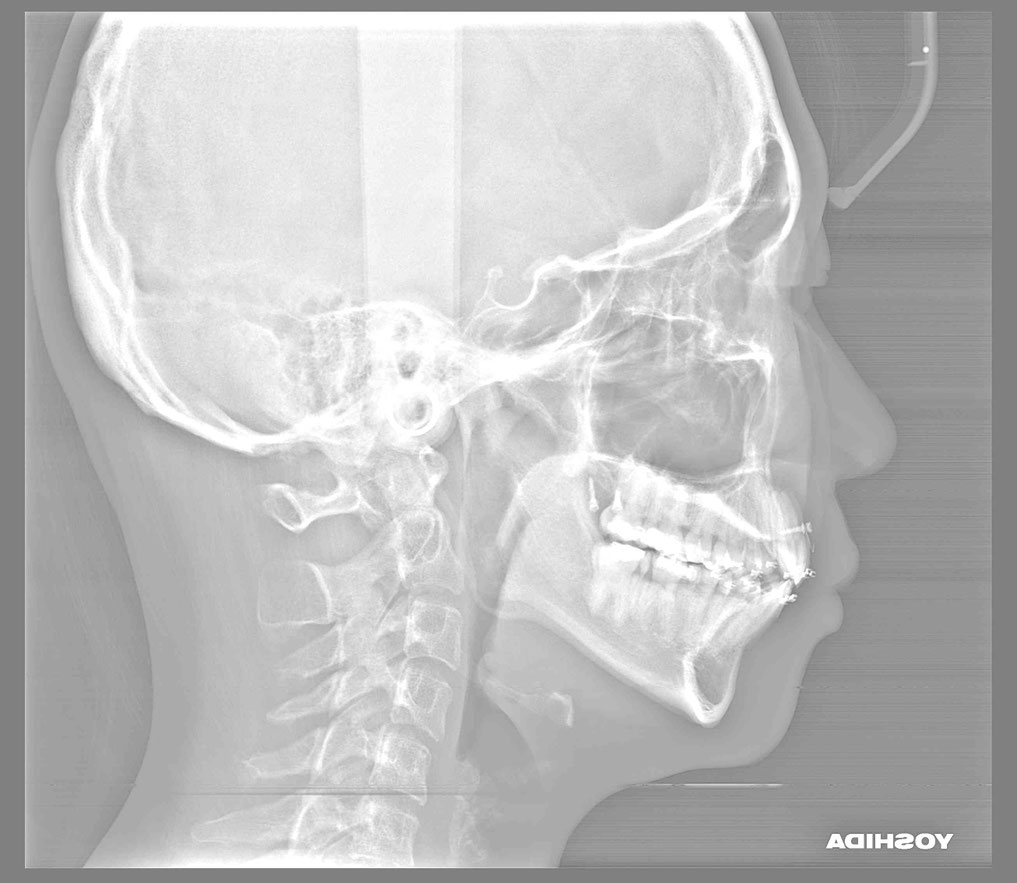

矯正治療が終わり、歯並びはきれいに整いました。

矯正治療後に奥歯の歯ぐきが2~3ミリ退縮。

治療後の変化

再生治療により、

2~3ミリ下がっていた歯ぐきが回復。

歯の長さが自然なバランスに戻り、

厚みのある丈夫な歯ぐきが再建されました。